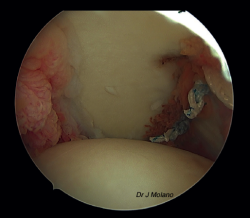

Una vez realizada la reparación de Bankart, se cambia nuevamente el artroscopio al portal anterosuperior y desde el posterior vamos recuperando los 2 cabos de cada sutura a nivel del Hill-Sachs para anudarlos, en el espacio subacromial, de inferior a superior (habitualmente 4 suturas), consiguiendo el relleno del defecto de Hill-Sachs.

Figura 7. Visión artroscópica desde el portal superior tras anudado de remplissage, implantación intraarticular de la ligamentoplastia y reparación capsulolabral que oculta el ligamento.